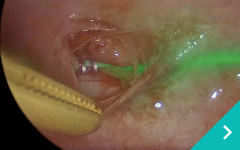

東京どうぶつ低侵襲医療センターでは、大切なご家族である動物たちの体への負担をできる限り軽減するために、 低侵襲(ていしんしゅう)技術を用いた診断・治療を行っています。 内視鏡や腹腔鏡、血管内治療などの先進的な医療機器と専門知識を駆使し、「きずが小さく、痛みが少ない」ことを追求。 術後の回復も早く、入院期間の短縮にもつながります。また、各分野の専門獣医師が連携し、安心・安全なチーム医療を提供しています。

動物たちにやさしく、飼い主さまにも安心していただける医療を目指しています。

腹腔鏡胸腔鏡

診療科目:腹腔鏡・胸腔鏡

『傷』が小さく、『痛み』が少ない手術・検査ができます!!

内視鏡外科(低侵襲)を希望のかたは東京どうぶつ低侵襲医療センター・王子ペットクリニックに相談ください。